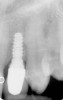

Figure 1  Radiograph demonstrating retained excess cement on abutment (see arrow).

Figure 1